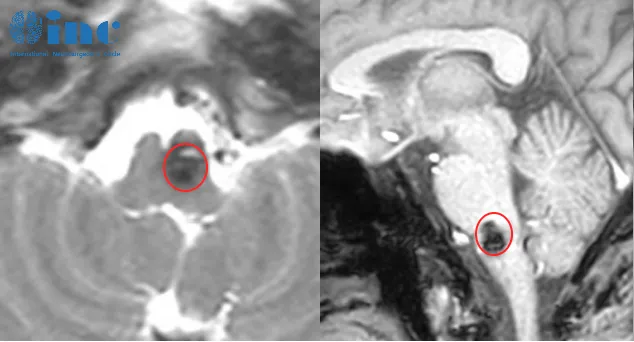

脊髓海绵状血管瘤,这个大多数人从未听过的疾病,没有给郑先生任何缓冲的机会。吞咽、抬手、翻身这些与生俱来的能力,在一夜之间成了遥不可及的奢望。 突遭变故:从生意场高手到重症...